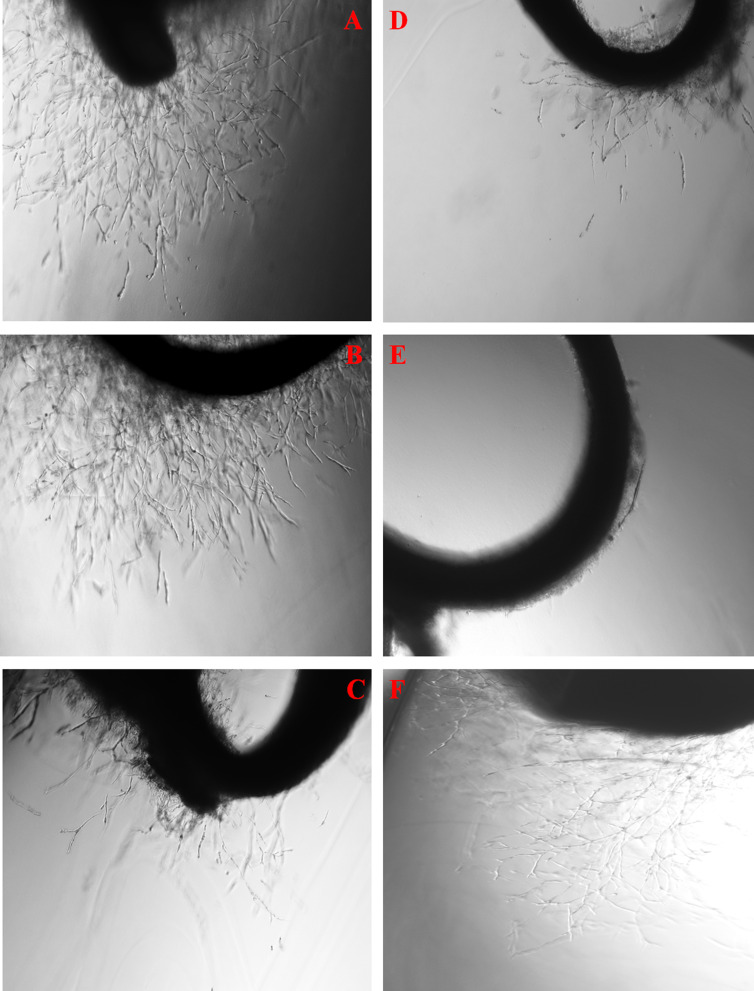

Results: MTT cell viability experiments showed that oleo-gum resin extract induced moderate cytotoxicity towards EA.hy926 cells (IC50 = 42 µg/mL). Extract-treated cells showed significant reduction in invasion, migration, and tube formation potential. At the protein level, down-regulation in expression of angiopoietin-1 and -2, Tie-2, MMP-1 and -9, VEGF-A, and VEGFR2 pro-angiogenic proteins was observed in extract-treated EA.hy926 cells. Signalling array data indicated a marked down-regulation of transcription factors, i.e., HIF-1α and WNT (-3.68 ± 5.74 and -6.24 ± 6.50 fold-change). Furthermore, extract treatment diminished vessel-sprouting in in vitro 3D spheroids, ex vivo rat aorta ring, and in vivo chick embryo chorioallantoic membrane models. Treatment with extract significantly reduced intracellular ROS and caspases-8 and -9 levels. GC-MS and HPLC analyses of extract indicated the presence of (+)-α-longipinene, isoledene, cedrene and α-elemene. ADMET prediction of detected compounds revealed good intestinal absorption (> 90%) and skin permeability (log Kp < -2.5), making the extract a suitable candidate for the treatment of angiogenesis-associated intestinal and skin disorders.